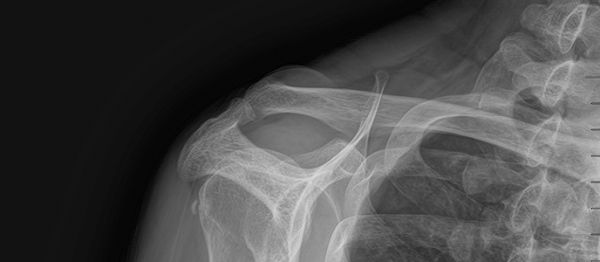

석회쇄석흡인술 페이지 정보 작성자최고관리자 등록일 2025-02-25 17:44 조회28 본문 치료 증상 잘 때도 아파서 깸 , 팔 들기 힘듦 나이 / 성별 50세 / 여성 치료내용 석회쇄석흡인술 후 호전 치료기간 2025-02-22 ~ 2025-02-22 null 목록 이전글석회쇄석흡인술 25.02.25 댓글 0 댓글목록 등록된 댓글이 없습니다.